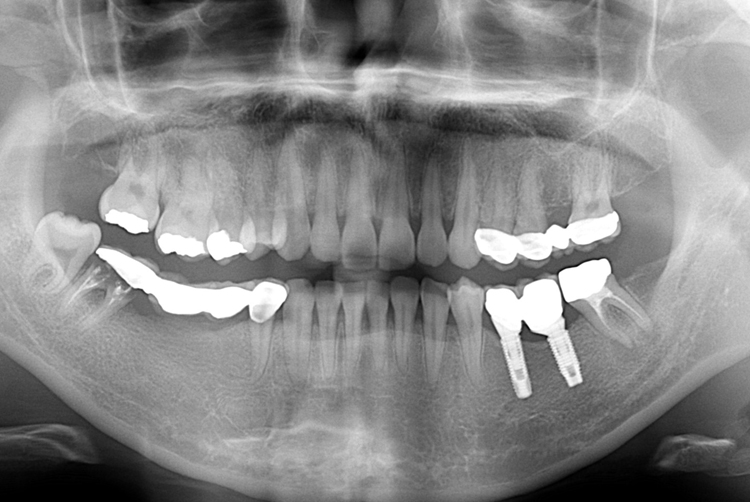

[임플란트] 어금니 임플란트

치료전 : 2018-08-01

세종치과는 많은 환자와 다양한 케이스를 바탕으로

항상 편안한 임플란트 수술을 제공하고자 노력하고,

오래동안 튼튼히 쓸 수 있는 임플란트 수술을 가장 큰 목표로 삼고 있습니다.